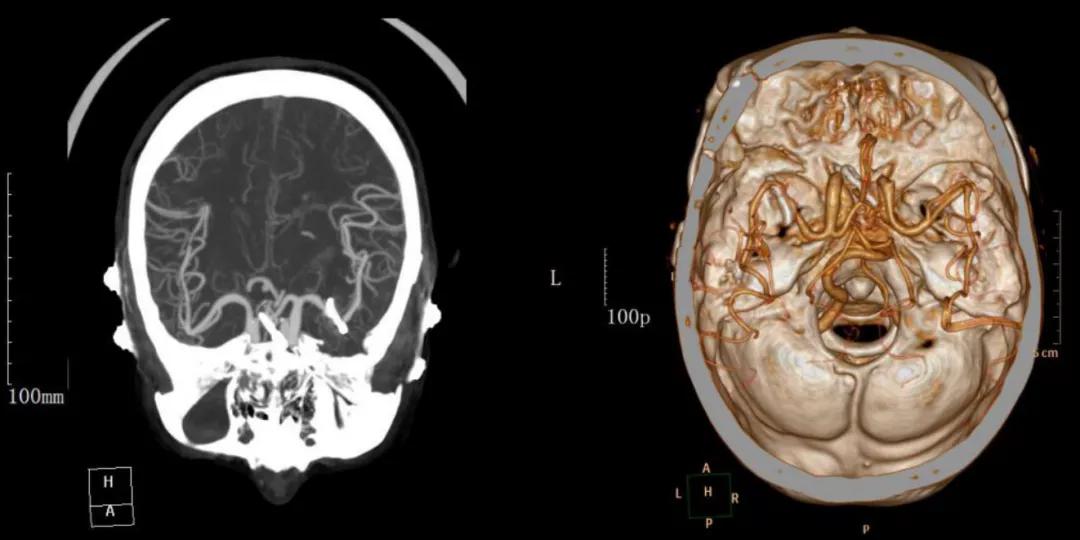

术后影像学资料:

术后复查头颅CT动脉瘤夹闭术后,动脉瘤已成功夹闭,没有出现大面积脑梗塞及再出血等并发症。林奶奶意识逐渐清楚,四肢活动良好,无神经功能缺损,两周后痊愈出院。